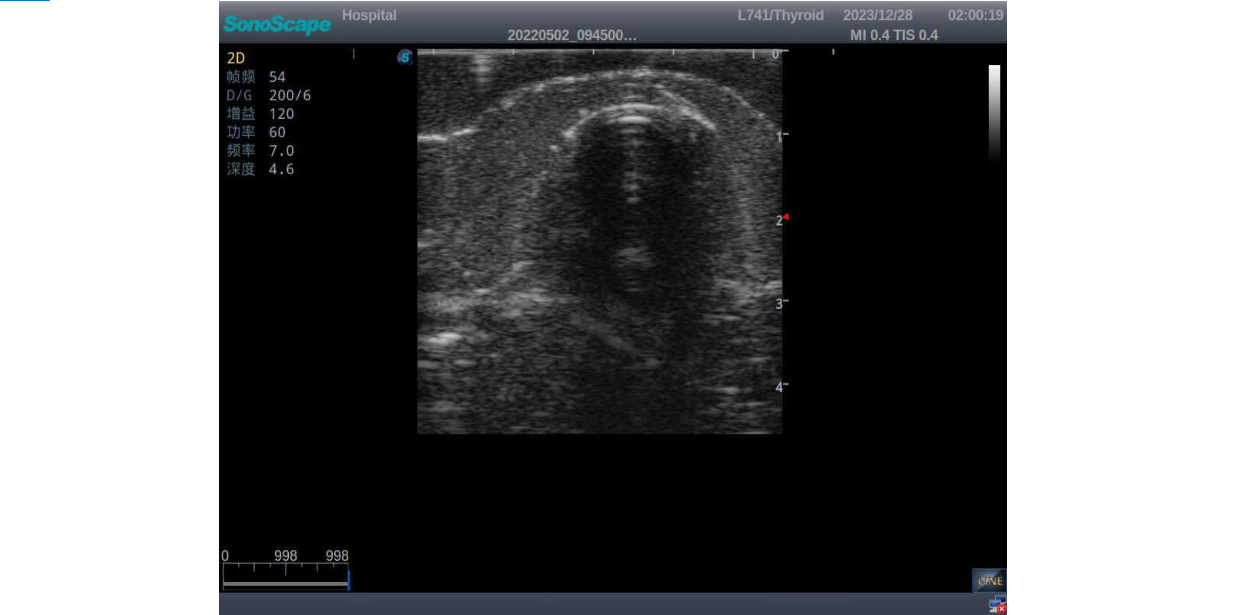

3)       It comes with four (4) thyroid modules and can show five (5) ultrasonic images: normal thyroid, thyroid adenoma, thyroid cancer, nodular goiter, thyroid cyst

Thyroid cancer with irregular mass, unclear border, uneven internal echo or calcification strong echoes